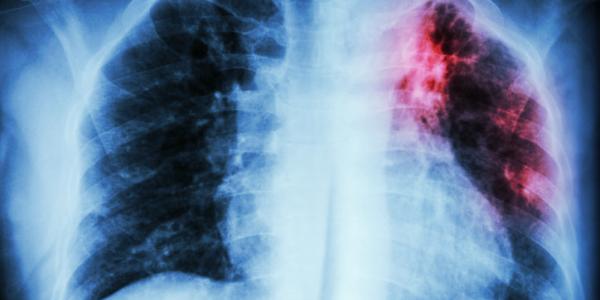

Tuberculosis

Hoy se conmemora el Día Mundial de la Tuberculosis, en tiempos de Covid-19

Esta enfermedad, lejos de ser erradicada, es una de las primeras causas de origen infeccioso en el mundo.

España se sitúa a un paso de la cura de la tuberculosis

SALUD Y ESTILO DE VIDA